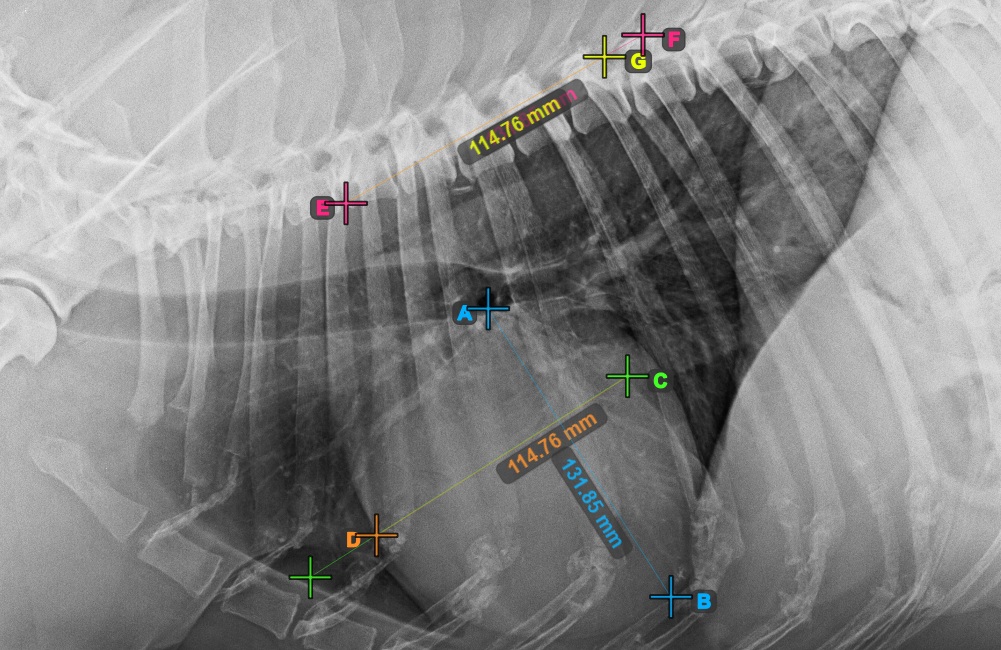

The image below represents a typical placement of the most cranial point on the short axis of the heart.

../../_images/image395.jpg